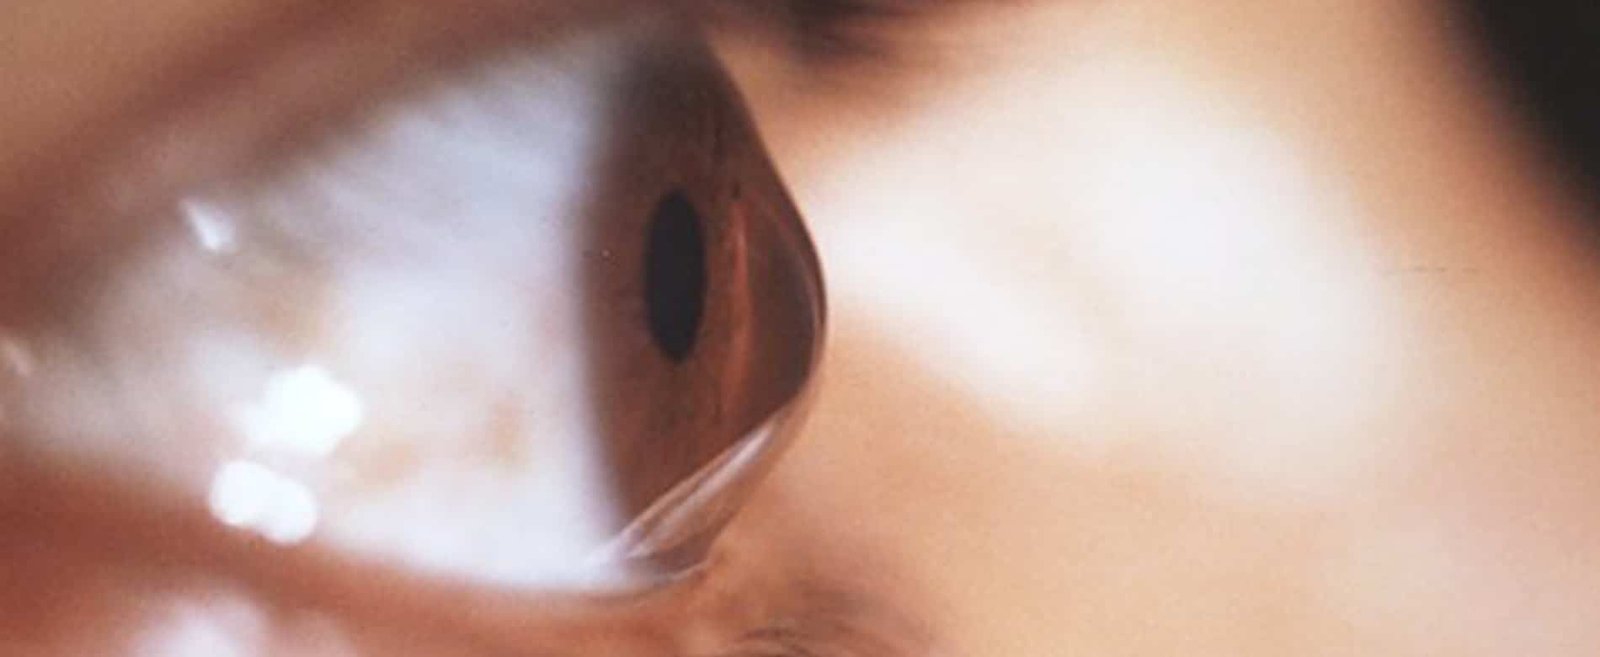

C’est une déformation de la cornée (le revêtement transparent de l’iris et de la pupille de l’oeil) qui s’amincit progressivement, perd sa forme sphérique normale et prend une forme de cône irrégulier.

Cette déformation, qui survient dès l’âge de 5ans et peut s’arrêter vers la trentaine, engendre des troubles de la vision (vue brouillée et déformée et mauvaise vision de loin) qui nécessitent le port de lentilles spécialisées.